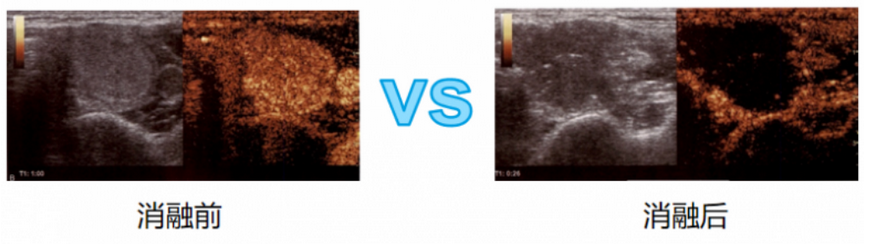

【造影技术】

使用造影剂后散射回声增强,明显提高超声诊断的分辨力,敏感性和特异性的技术。在甲状腺乳腺结节消融前、中、后的评估都起到了重要作用。消融前治疗规划:

※ 优于常规超声。

※ 准确反映甲状腺结节微循环灌注。

※ 设计最佳进针路线。

※ 分辨甲状腺和周围组织的结构关系。